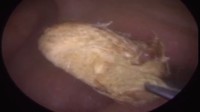

Ini dia kapas yang lama tersangkut di telinga. Warnanya sudah coklat pekat. (Foto: Youtube/Caters Clip)